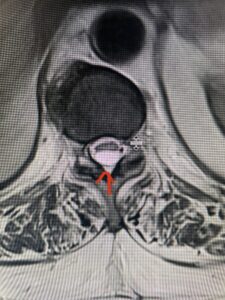

This 47-year-old male who four months prior was lifting weights developed sharp pain in his neck. After that he developed progressive numbness in his arms, neck pain and headache. He said that the right arm was worse than the left. On examination the patient had long tract weakness on the right side which included his triceps, finger extensors, hip flexors, and dorsiflexors. The patient did not have hyperreflexia. MRI (Fig. 2) demonstrated a massive, extruded disc herniation with severe cord compression. The patient because of progressive myelopathy and spinal cord compression was indicated for anterior cervical discectomy and fusion at C4-5 (Fig. 3). Patient had significant improvement of weakness and numbness post operatively.

Fig. 2a Sagittal T2-weighted cervical MRI demonstrating large C4-5 herniated disc with spinal cord compression (red arrow)

Fig: 2b Axial T2-weighted cervical MRI demonstrating spinal cord compression from C4-5 herniated disc (red arrow)